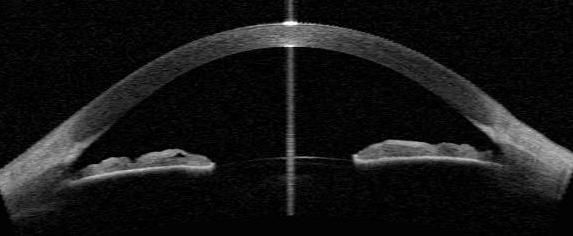

In some cases, OCT is used to gather information about the front of the eye (anterior segment), which includes structures such as the cornea, iris, and the anterior chamber angle. This type of OCT can be helpful for diagnosing and monitoring diseases of the cornea, as well as planning and performing surgery.

An OCT scan of the front of the eye showing the cornea, iris, and anterior chamber.